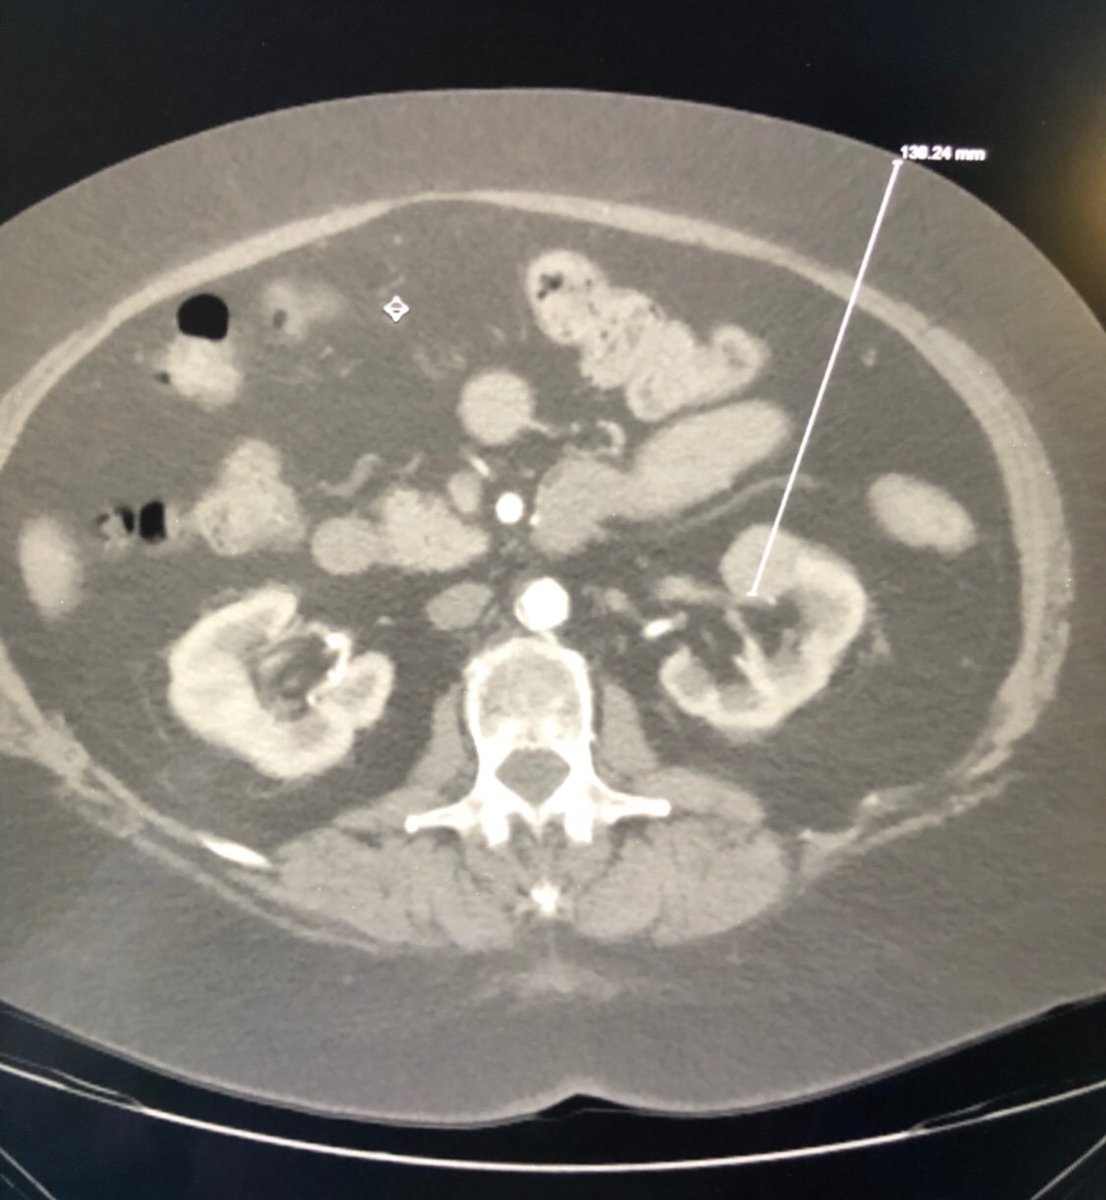

New study @AnnalsofIM bit.ly/2Km3KYu by @DrTalenfeld @WeillCornell: Percutaneous ablation for T1a #renalcancer has similar 5-year survival rates to radical nephrectomy but with far fewer 30-day complications and less #kidneyfailure.